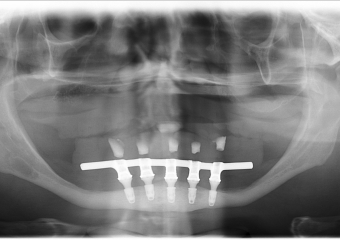

Raio - x Panorâmico Implantes inferiores instalados, em Outubro de 2015

Raio-x Implantes com Prótese Fixa Definitiva em Resina